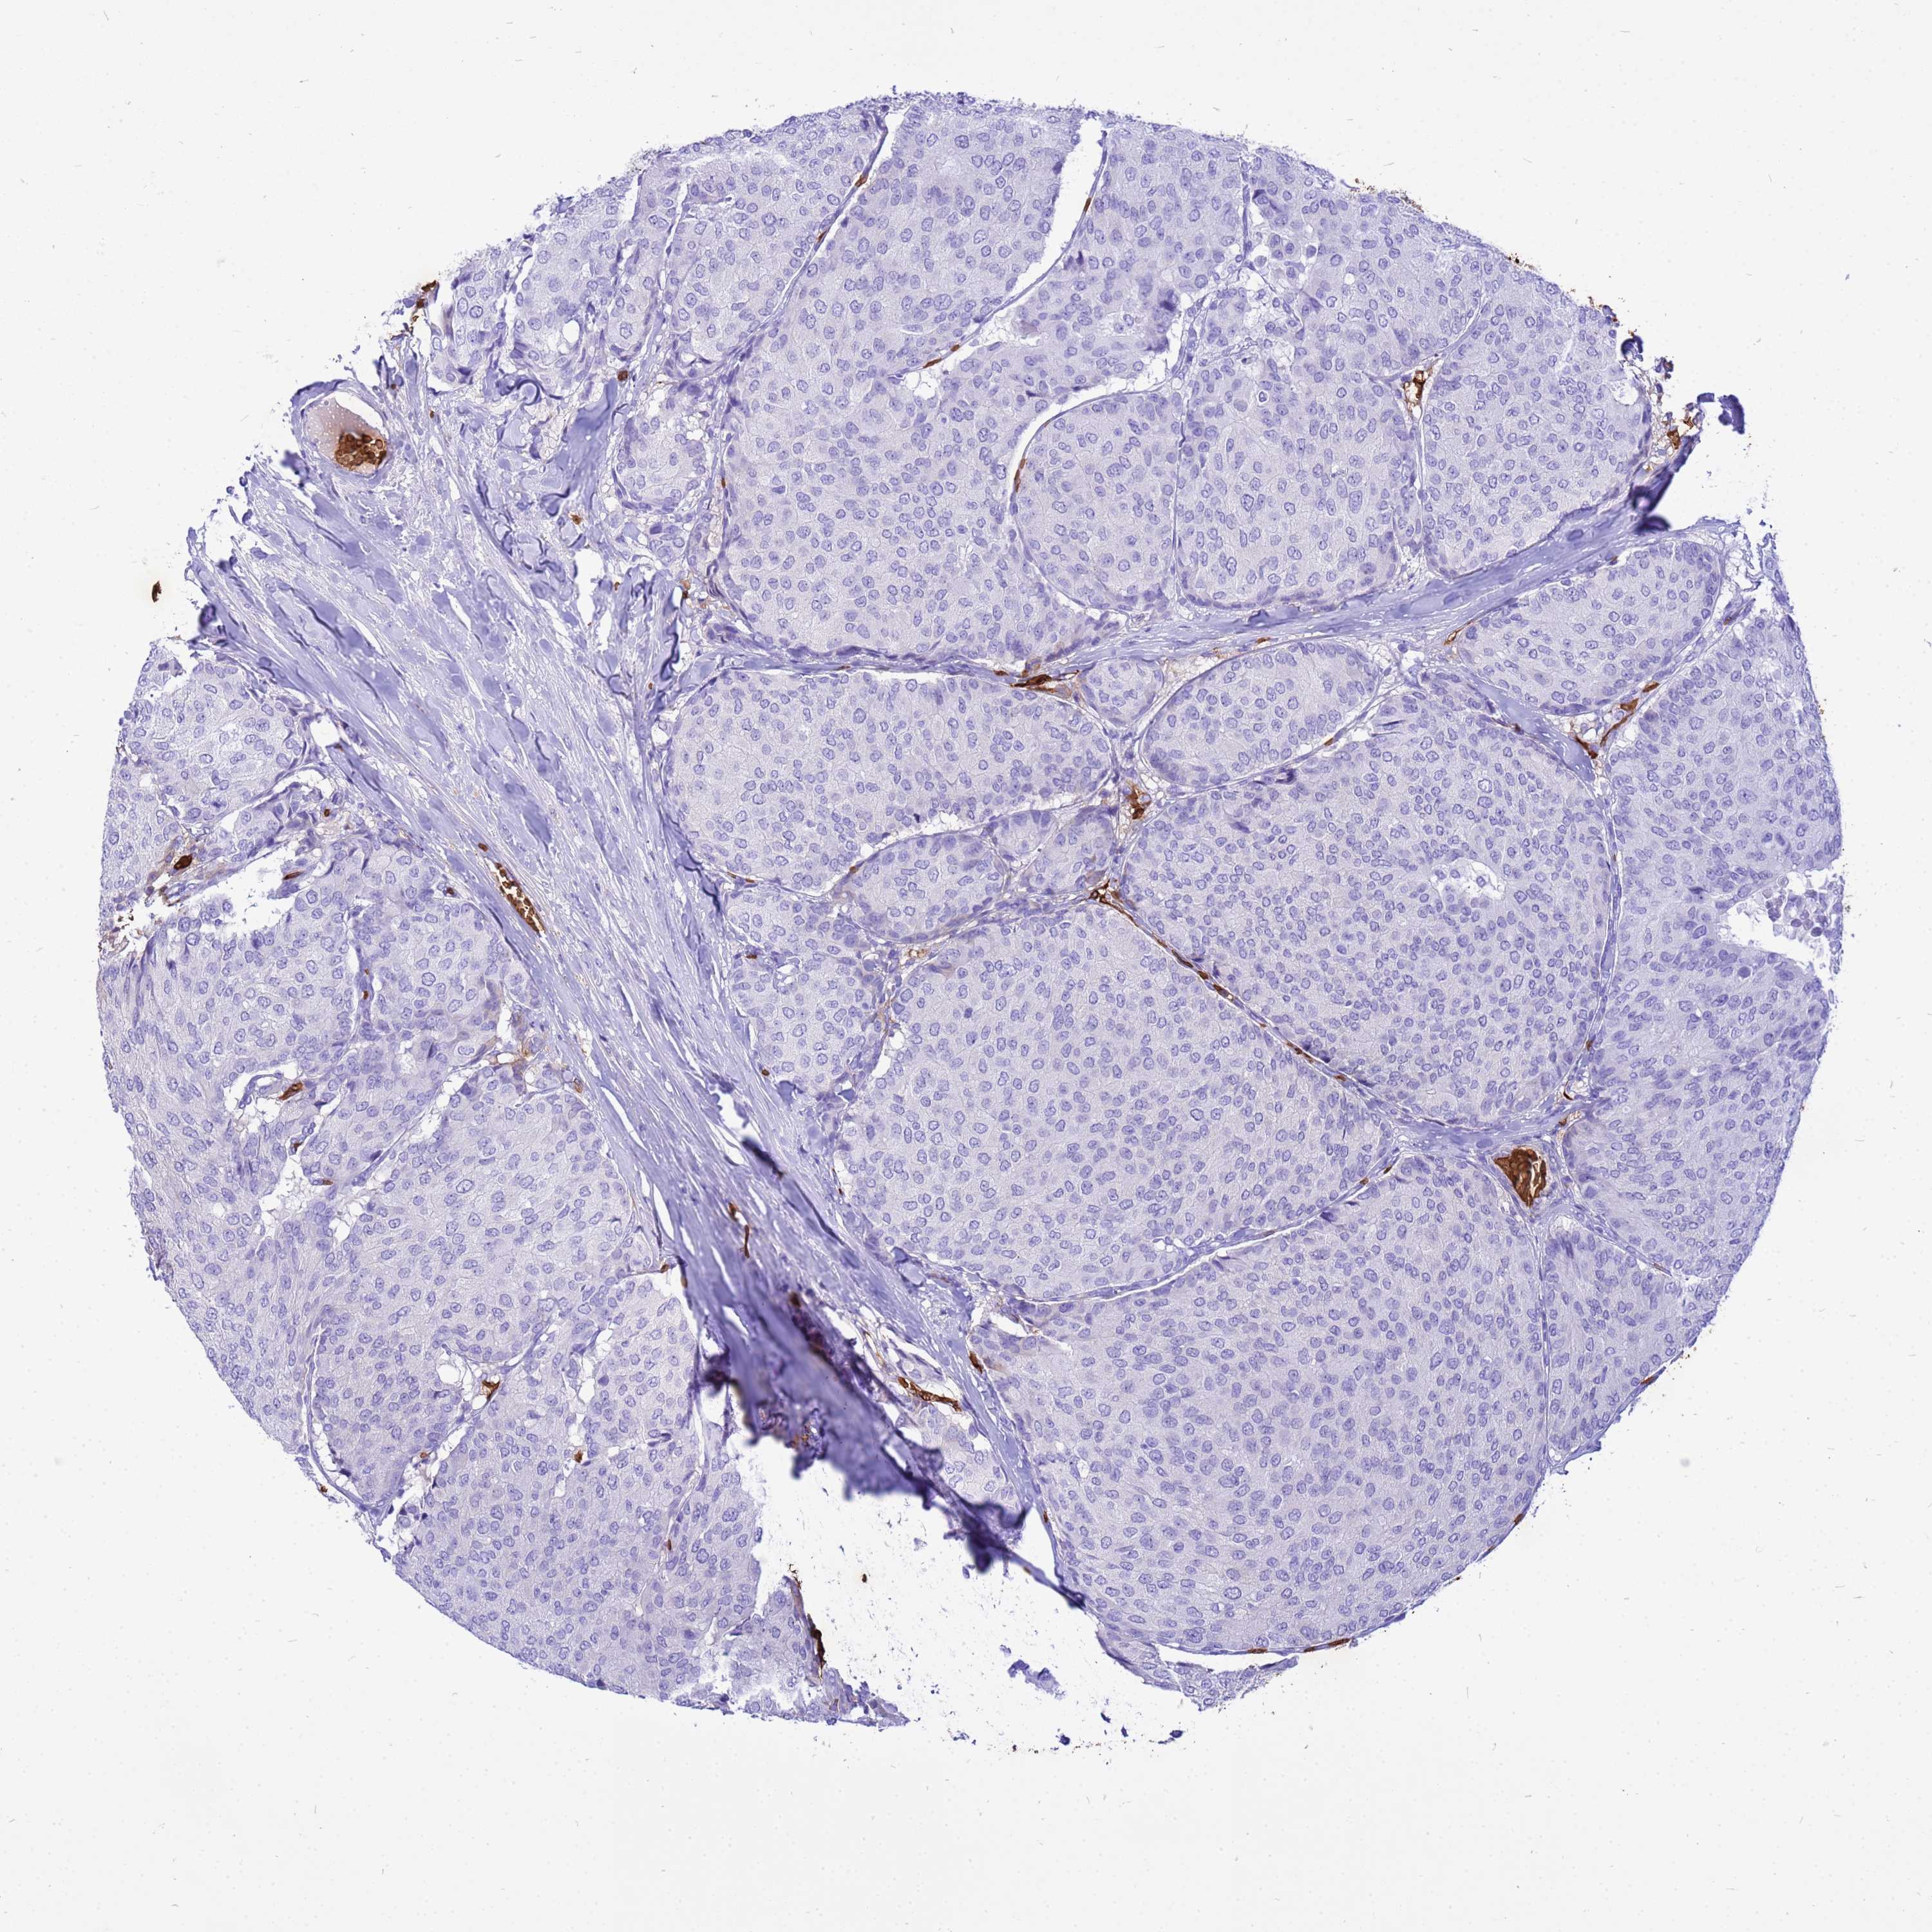

BRCA TCGA BRCA VALIDATION PROTEIN EXPRESSION

ANTIBODIES

AND

VALIDATION